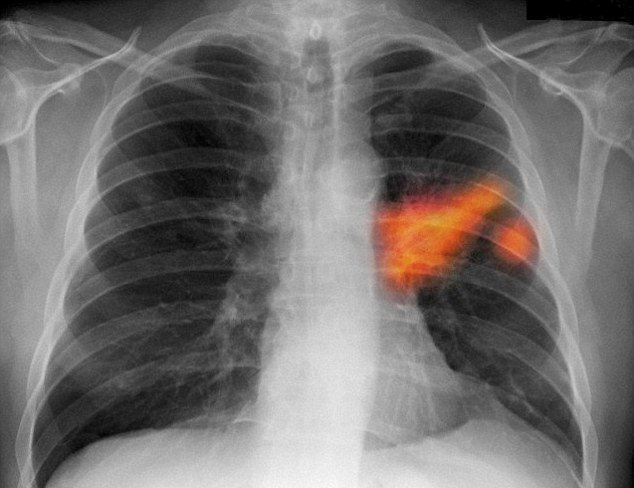

Bạn đã từng nghĩ rằng một người thân của bạn bình thường vốn rất khoẻ mạnh, không đau ốm, vậy mà chỉ qua một đêm lại mắc căn bệnh nan y? Ngày ngày lo lắng một mai khi bạn tỉnh giấc thấy người nằm bên cạnh mình đã qua đời vì bệnh. Hiện nay tôi đang bị dằn vặt bởi tâm trạng này, tôi và chồng tôi Đinh Quang Hà đã sống một cuộc sống bình yên bên nhau suốt ba mươi mấy năm, nhưng tháng 7 năm 2014 lại kiểm tra thấy phổi trái của chồng tôi có khối u và được xác định là ung thư phổi. Tôi và các con biết được chồng mình đã mắc phải căn bệnh được coi là “nan y” này, hằng ngày đều lo sợ chồng tôi sẽ bị quỷ thần mang đi ngay trước mắt, càng buồn và lo lắng cho chồng bị sự dày vò của bệnh tật.

Bác sĩ Jang phụ trách điều trị cho chồng tôi ngày nào cũng đến phòng bệnh để tìm hiểu sự thay đổi bệnh tình, ăn uống, tinh thần và sinh hoạt của chồng tôi có gì thay đổi hay không, các y tá nhiệt tình và vui tính đã giúp đỡ chúng tôi rất nhiều, quan tâm và chăm sóc tận tình cho tình trạng sức khoẻ của chồng tôi. Sau phẫu thuật, thông qua kiểm tra chụp CT, bác sĩ Jang nói rằng khối u ban đầu có kích thước 7x5cm của chồng tôi sau điều trị đã nhỏ đi 2-3cm, triệu chứng của bệnh cũng được cải thiện nhiều. Biết được bệnh tình của chồng tôi đã có tiến triển tốt, tôi cảm thấy rất vui mừng, áp lực từ khi chồng tôi mắc bệnh cũng đã dịu dần.